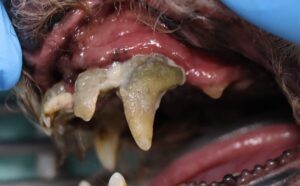

- 左下顎第一後臼歯に歯石を認める

- 歯肉が浮腫状に腫れ、赤みが強い

歯肉縁上、下のスケーリングとポリッシングを行いました。